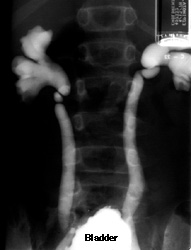

Reflux Seen on Voiding Cystourethrogram (VCUG)

A 10-year-old girl had urine infections. Her ultrasound showed two normal kidneys. This is her VCUG.

The film was taken during voiding. The bladder is full and contrast is seen to travel in retrograde fashion up both ureters (reflux). Notice that there is no nephrogram (no contrast in the renal parenchyma). This tells us that this image was obtained by putting contrast into the bladder, not by injecting contrast intravenously (intravenous pyelogram or IVP).